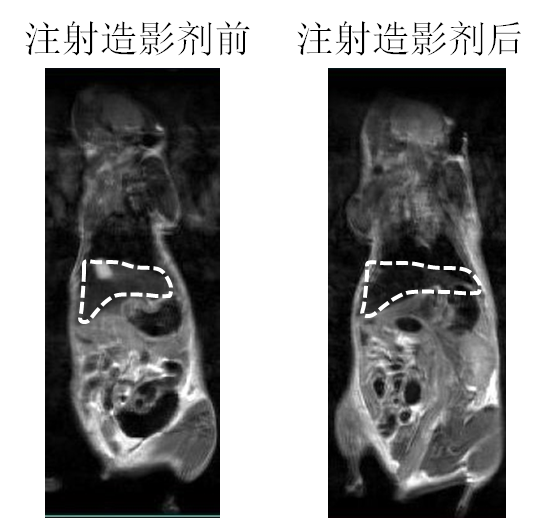

´ÅÐÔÄÉÃ×Á£×ÓÓÃ×÷´Å¹²Õñ³ÉÏñ£¨MRI£©ÔìÓ°¼Á

ÒÔǰֻÊÇÔÚÓ¡ÏóÖУ¬ÎªÁËÕâÊÂÕÒÁËһϣ¬»¹Ã»ÓÐÀ´µÃ¼°ÈÏÕæ¶Á¡£Ï£ÍûÓÐÖú http://www.ema.europa.eu/docs/en ... /01/WC500067464.pdf from wiki: http://en.wikipedia.org/wiki/MRI_contrast_agent Iron oxide: Superparamagnetic[edit] Two types of iron oxide contrast agents exist: superparamagnetic iron oxide (SPIO) and ultrasmall superparamagnetic iron oxide (USPIO). These contrast agents consist of suspended colloids of iron oxide nanoparticles and when injected during imaging reduce the T2 signals of absorbing tissues. SPIO and USPIO contrast agents have been used successfully in some instances for liver tumor enhancement.[17] Although SPIOs and USPIOs have been approved for use in the past, it appears that all of the agents listed below are no longer available with the exception of the oral iron oxide contrast agent, Lumirem/Gastromark. Feridex I.V. (also known as Endorem and ferumoxides). This product was discontinued by AMAG Pharma in November 2008.[18] Resovist (also known as Cliavist). This was approved for the European market in 2001, but production was abandoned in 2009.[19] Sinerem (also known as Combidex). Guerbet withdrew the marketing authorization application for this product in 2007.[20] Lumirem (also known as Gastromark). Gastromark was approved by the FDA in 1996.[21] Clariscan™ (also known as PEG-fero, Feruglose, and NC100150). Development was discontinued due to safety concerns.[22] |